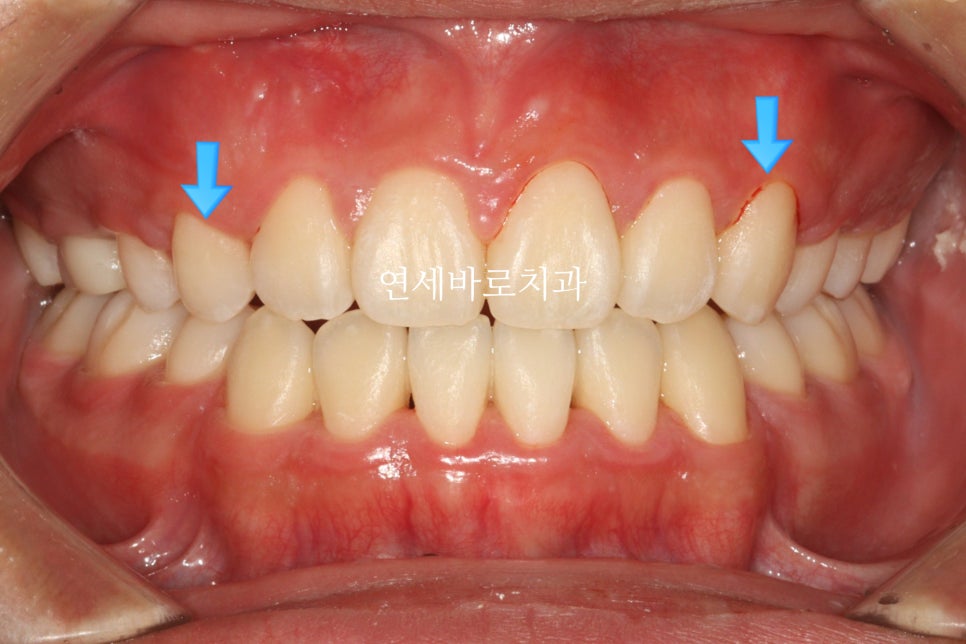

시작 전 모습입니다.

어머니도 아이가 매복치아가 있는지 전혀 모르고 있다가 우연히 교정상담하러 와서 발견한 경우입니다.

그 심미적 문제가 이것입니다.

화면의 왼쪽은 작은 어금니

오른쪽은 송곳니 입니다.

그래서 모양이 다르죠.

이런문제가 있긴 하지만 거의 티가 나진 않습니다.

전과 후를 비교하며 작성을 마치겠습니다.